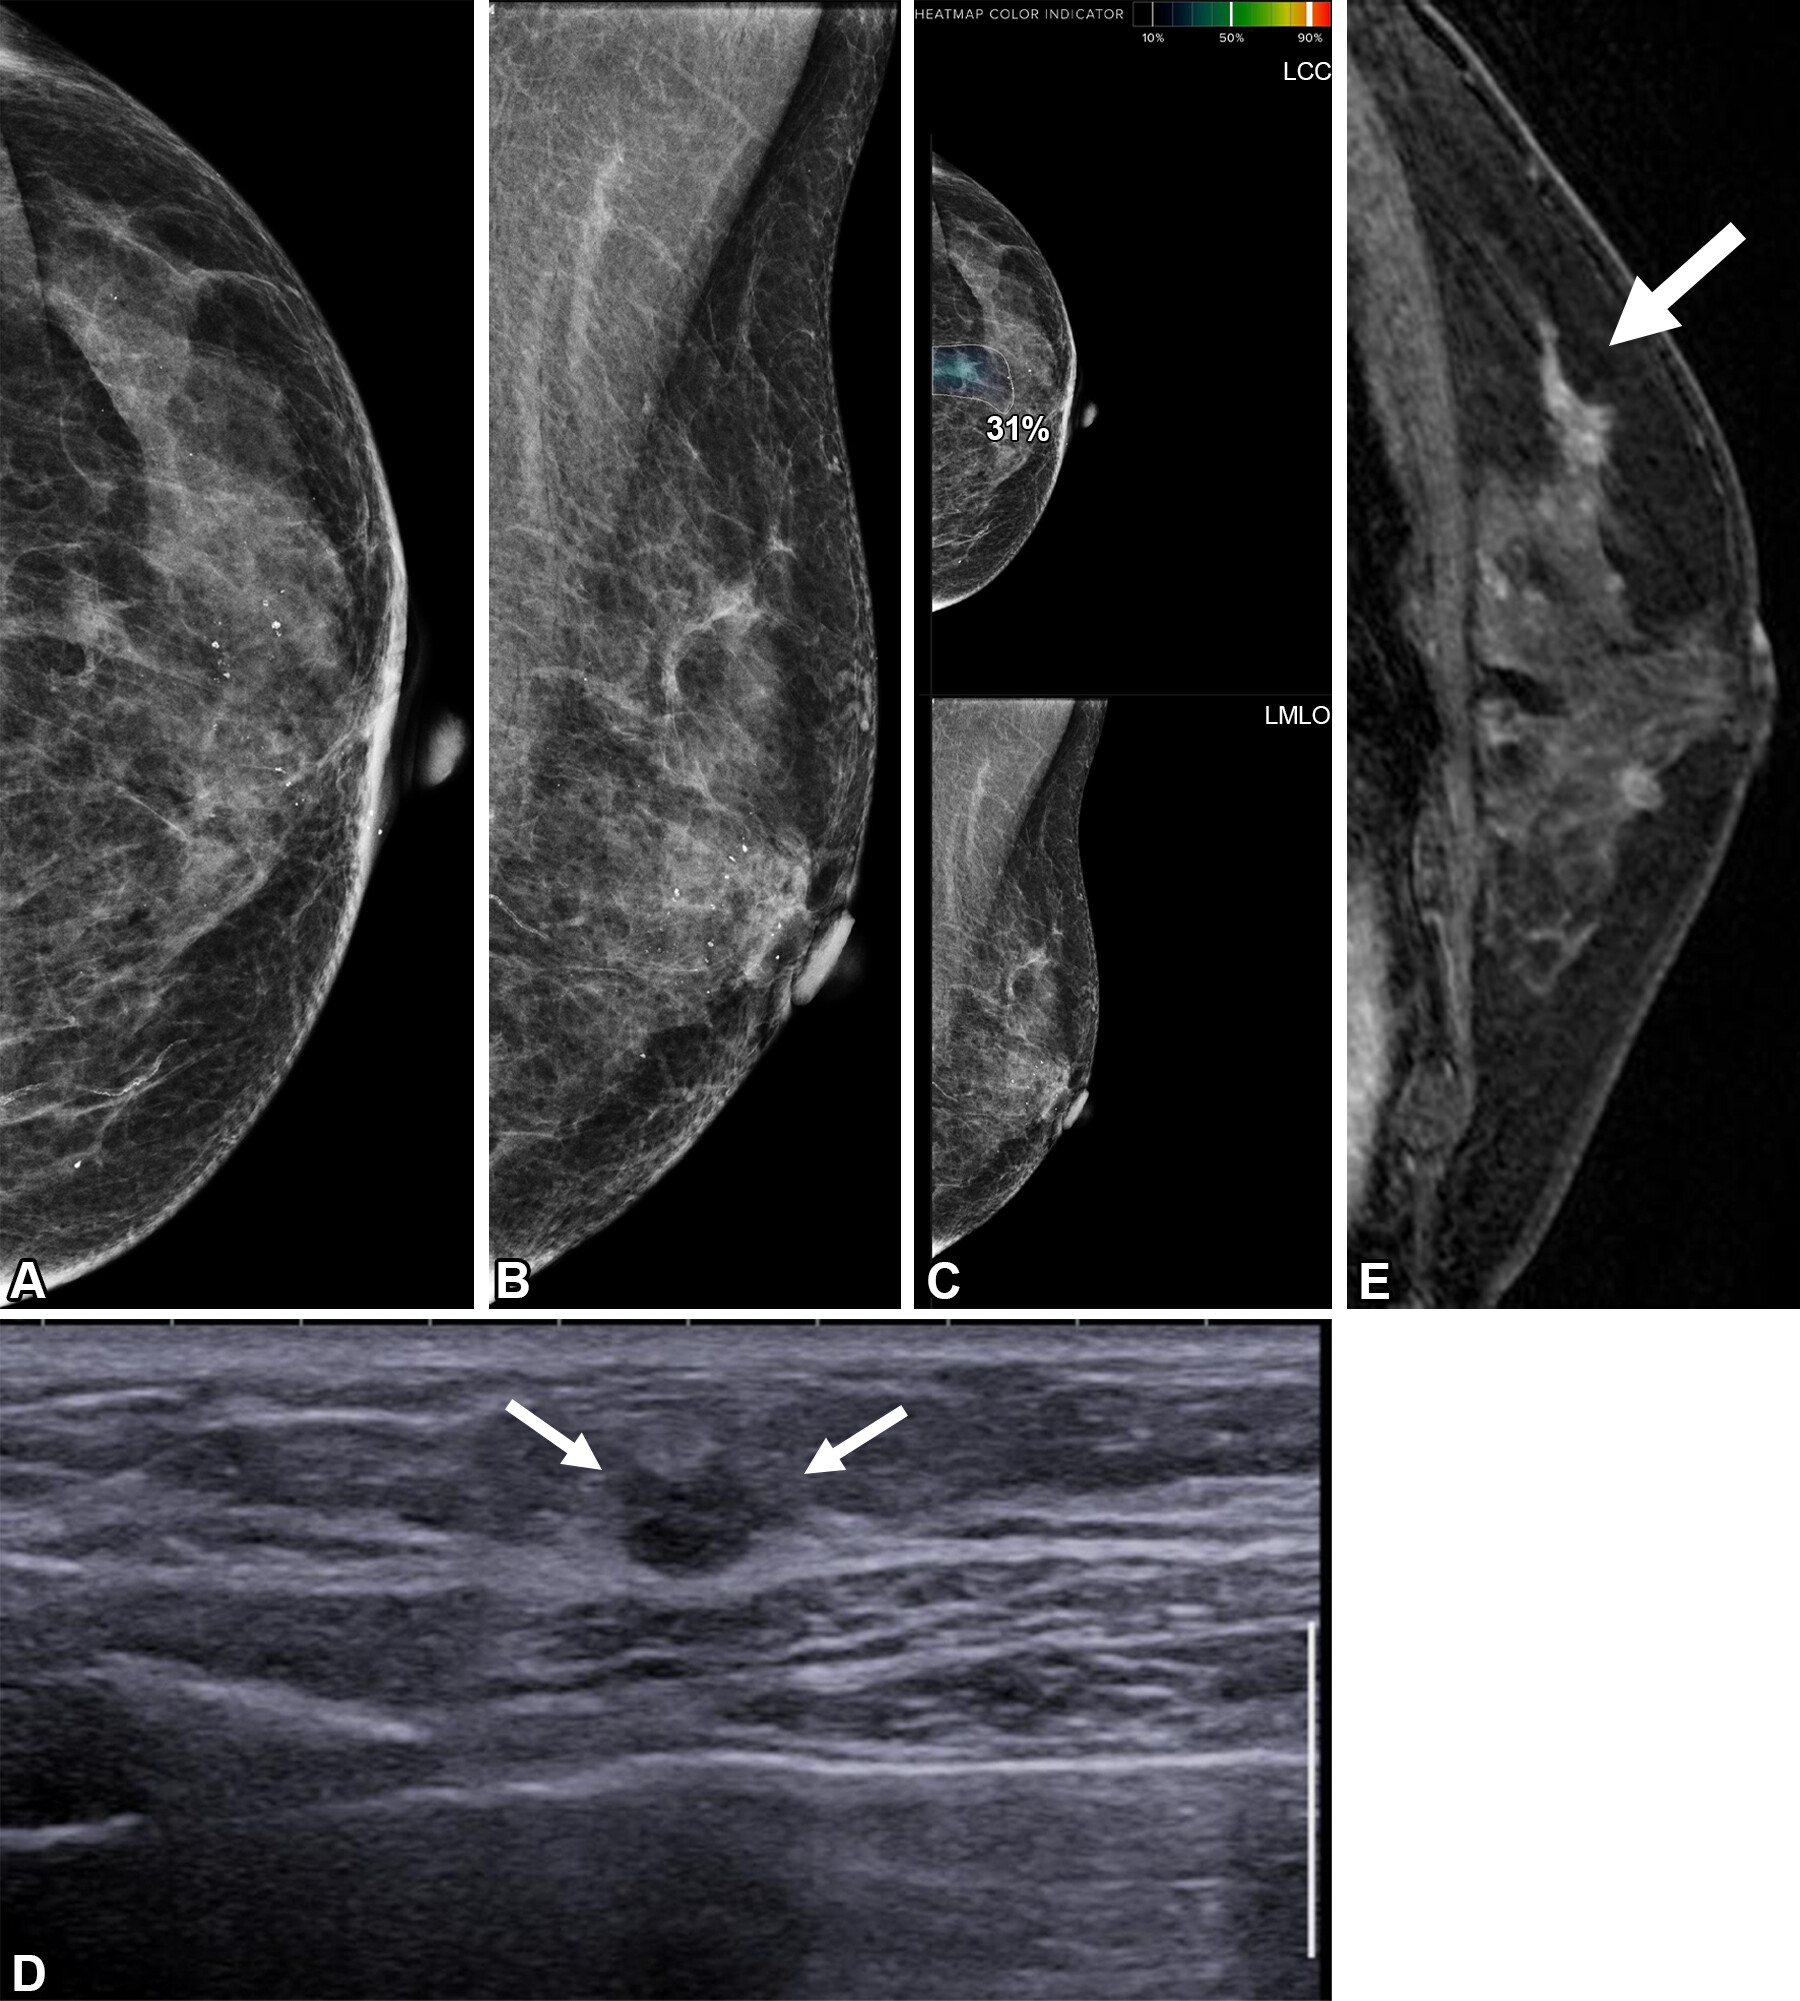

Images depict a 55-year-old woman with a family history of breast cancer who underwent combined mammography and MRI screening. (A) Right and (B) left mediolateral oblique and (C) right and (D) left craniocaudal mammograms show a large known cyst in the left breast (arrow in B and D), but were otherwise assessed as being unremarkable. Breast tissue was judged to be extremely dense. (E) Concurrent axial subtraction MRI scan shows a large, diffuse, invasive lobular cancer (circle) in the right breast. The AI system provided a case-based cancer suspicion score of 8 on a scale of 0-10, which would have led to selection for MRI screening using both the score 5 and score 8 thresholds, but not the score 9 threshold.RSNA